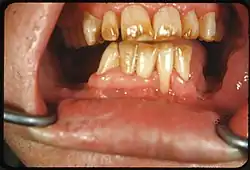

• Calculus: Neglected plaque eventually calcifies, and leads to formation of a hard deposit on the teeth, especially around the gumline. The color of calculus varies, and may be grey, yellow, black or brown.[12]

• Tobacco: Tar in smoke from tobacco products (and also smokeless tobacco products) tends to form a yellow-brown-black stain around the necks of the teeth above the gumline.[12]